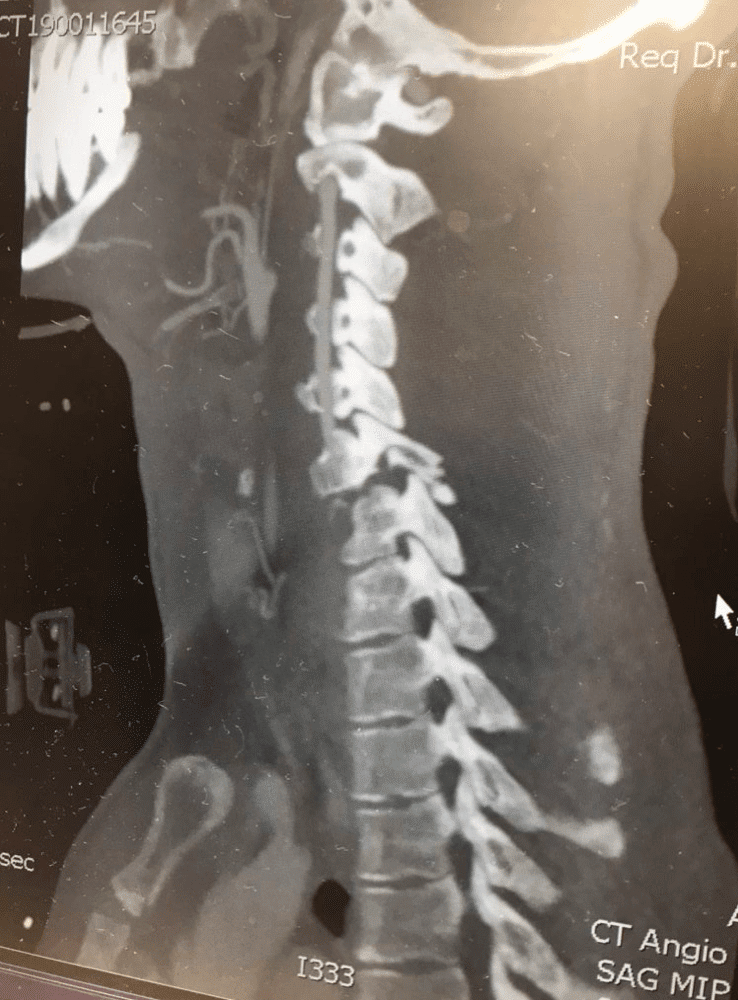

Earlier this month on January 14, 2019, Blake Savage crashed while riding at a private supercross track in Mesquite, Nevada, sustaining a cervical spinal cord injury due to fractures to his C6 and C7 vertebra. Savage was immediately transported to Dixie Regional Medical Center in St. George, Utah, where his injuries were assessed and a surgical plan was quickly put into place. On Tuesday, January 15, Savage underwent successful surgery, where doctors completed a C5 to T1 posterior spinal instrumentation and fusion, which addressed the fractures and stabilized the spine.